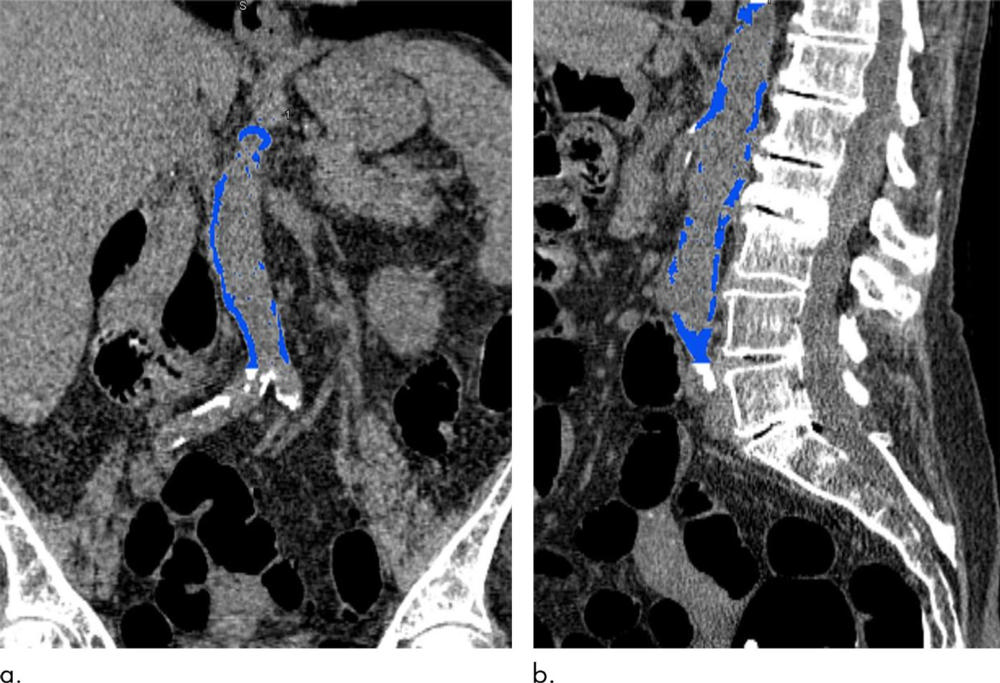

Figure 1. Images from CT colonography show segmented abdominal aortic calcification measured with semiautomated CT tool on (a) coronal and (b) sagittal images. Within region of interest over aorta selected by user, tool automatically segments and quantifies aortic calcification (shown in blue).

CT can also measure calcium in the abdominal aorta, the large vessel that carries oxygenated blood to the lower extremities. The abdominal aorta can be seen on abdominal imaging exams like CT colonography, also known as virtual colonoscopy, and in the diagnostic workup for acute cholecystitis, an inflammation of the gallbladder often caused by gallstones.